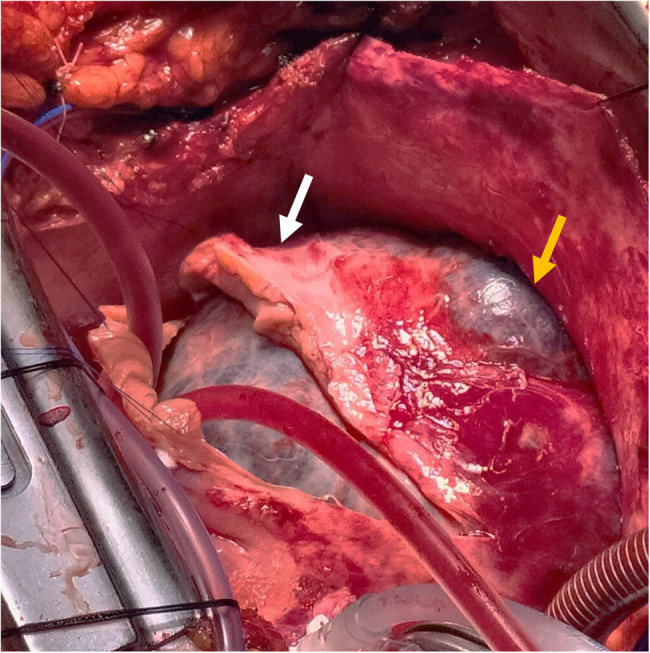

Methods: We report herein the case of a 72-year-old woman with a giant right atrial mass. The patient suffers from abdominal swelling related to ascites. The histological examination of the tranjugular biopsy suspected an atrial myxoma.

Results: The patient was scheduled for surgical excision of the cardiac tumour. Radical resection of a 13 cm mass was performed. The histological diagnosis revealed cardiac hemangioma.